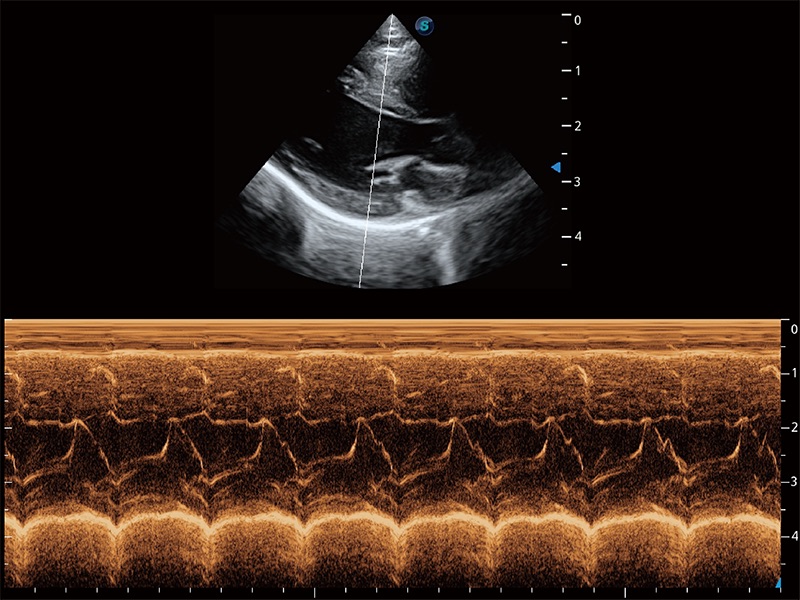

ProPet 80 配備了豐富的心臟探頭群、先進(jìn)的成像技術(shù)和專業(yè)的心臟測量工具,可幫助動物醫(yī)生為不同體型和生理結(jié)構(gòu)的動物提供心臟和心肌功能的全面評估。

通過360度任意調(diào)節(jié)3條M型取樣線,在同一心動周期上觀察心臟不同位置的運(yùn)動曲線,得到準(zhǔn)確的心功能測量數(shù)據(jù),有效評估心肌運(yùn)動及左心室功能。